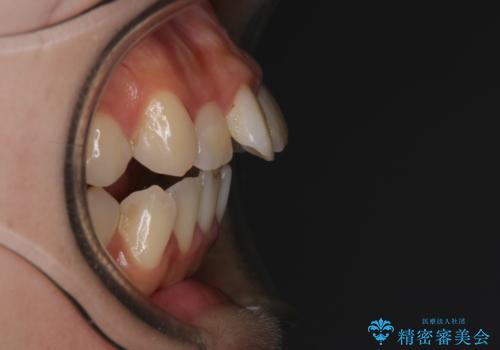

【インビザライン】マウスピースで開咬改善

- 開咬を主訴に来院されました。

IPR(歯と歯の間を削る処置)と顎間ゴムを行いながら、インビザラインで開咬を治療する計画を立てました。

治療をしながら、MFT(口腔筋機能療法)も行っていくことにしました。

歯の移動量が多いケースでしたが、患者様にマウスピースの使用とゴム掛けを頑張っていただいたので

リファイメント1回のみで治療を終わることができました。